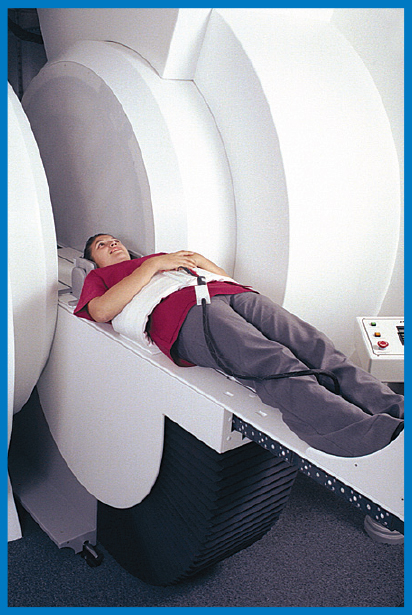

Recumbent

The Upright MRI is unlike any other scanner because it can scan patients in ANY POSITION. Other MRI scanners can only scan patients lying down. The Upright MRI can scan patients lying down too, but if the patient has, say, low back pain only when they are sitting or standing, does it make sense to scan them lying down? Only the Upright MRI can scan patients in their positions of symptoms, whatever they may be, including WEIGHT-BEARING positions, such as sitting, standing and bending. This unique ability has enabled the Upright MRI to provide more accurate diagnoses by detecting many problems that were underestimated or completely missed by other kinds of MRI’s.

The Upright MRI can provide diagnostic pictures of the neck (cervical spine), the lower back (the lumbar spine), and the joints of the body over their full range of motion. Flexion and extension views of the spine, for example, often provide critical information that doctors need in order to achieve the best results for their patients. No other MRI scanner can do this.